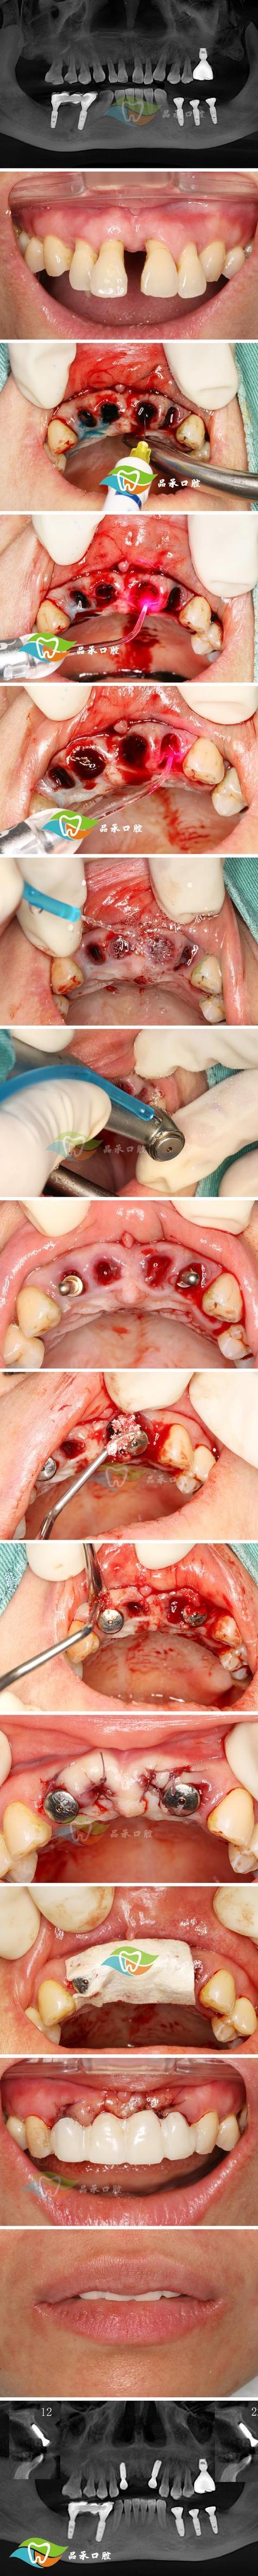

种植牙并非简单的“在牙槽骨里拧个钉子”,而是一项融合了医学、材料学、影像学的精密手术,医生需要通过CBCT获取患者颌骨的三维数据,设计种植体的植入位置、角度和深度,避免损伤神经、血管;对于牙槽骨条件不佳的患者(如骨量不足、骨密度低),还需进行植骨、上颌窦提升等附加手术,这些手术难度更高,耗材成本也更高(如骨粉、骨膜费用约2000-5000元/颗),数字化种植技术的普及(如3D打印导板、动态导航系统)能显著提高手术精准度,减少创伤,但这些设备本身价格昂贵(一台口腔CBCT可达数十万至数百万),其使用成本也会分摊到患者费用中,更重要的是,种植医生的经验和技术水平直接影响手术成功率——经验丰富的医生能应对复杂的口腔状况,减少并发症(如种植体周围炎、骨吸收),而培养一名成熟的种植医生需要10年以上的临床积累和持续学习,其技术价值也是费用的重要组成部分。